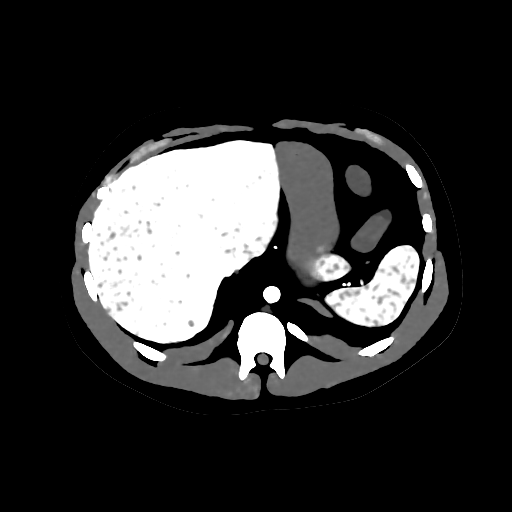

(digital human)